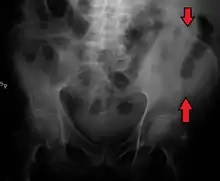

A fracture of the left iliac wing

The iliac crest has a large amount of red bone marrow, and thus it is the site of bone marrow harvests (from both sides) to collect the stem cells used in bone marrow transplantation. The iliac crest is also considered the most ideal donor site for bone grafting when a large quantity of bone is needed. For example, oral and maxillofacial surgeons will often use iliac crest bone to fill in large osseous defects of the oral cavity caused by severe periodontal disease, excess bone resorption following tooth loss, trauma, or congenital defects including alveolar clefts.[4]